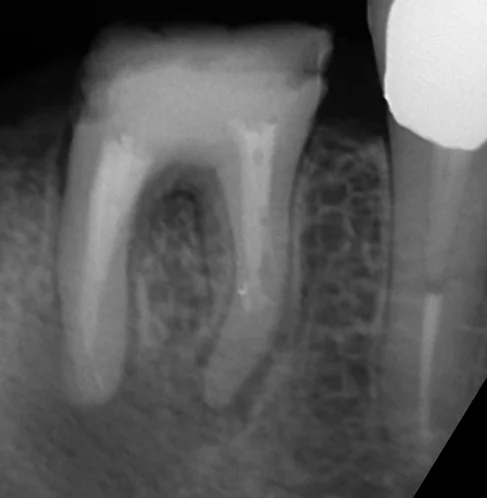

そしてその結果が、こちらです。

肝心の根尖病巣が入り切っていませんが、画像のトリミングの失敗です(笑)

注目して頂きたいのは、近心根ですが、実は根尖(根の先)まで全く行けていません。

大体2/3程度まで進んだのですが、それ以上は根管が石灰化していたため、全然進めませんでした。

それでも違和感が消失するのはそれなりに理由があるのですが、そこらへんはまたどこかでブログに書きたいと思います。